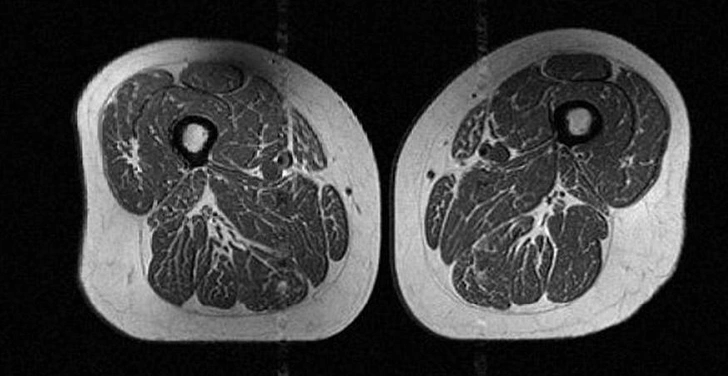

Жировые клетки ослабляют мышцы, становясь препятствием для их роста и мешая волокнам восстанавливаться. Слабые мышцы — ключевой фактор развития остеоартрита коленного сустава, самого распространенного заболевания суставов, которым страдают почти 375 миллионов человек в мире. Раньше остеоартрит считался болезнью пожилых, но исследование показало, что более половины новых случаев приходится на людей моложе 55 лет, что, вероятно, вызвано резким ростом ожирения в мире.

«Мышцы бедра имеют решающее значение для стабильности коленного сустава. Любая потеря их силы или тонуса увеличивает механическую нагрузку на сустав, особенно у людей с лишним весом», — говорит Аккая.

Наличие внутримышечного жира в бедре означает, что затронуты и другие мышцы тела, утверждает рентгенолог доктор Мириам Бределла из NYU Langone Health. «Это системный процесс. Можно посмотреть на икры, плечи или живот — картина будет схожей».

Снижение качества мышц из-за жировой инфильтрации означает потерю силы, что является предвестником будущих проблем: более длительного пребывания в больнице, осложнений после операций и даже риска рецидива опухолей.